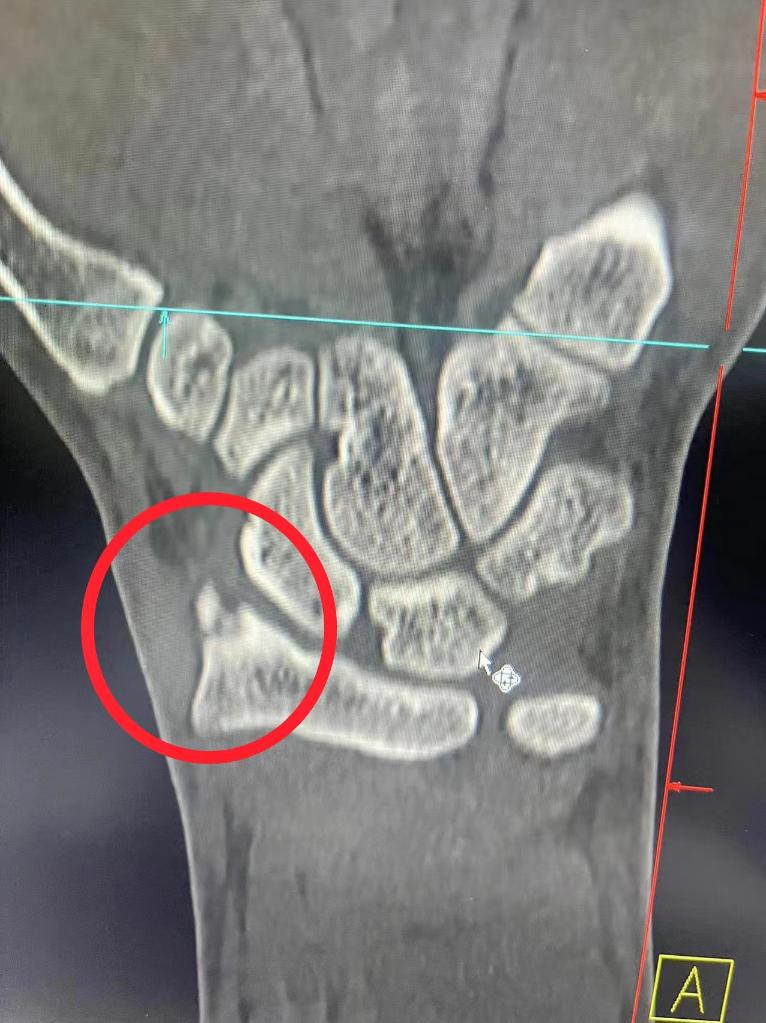

队友们将邹存涛送到医院检查

诊断为手部轻微骨折

经过石膏固定和消炎处理后

邹存涛回到队里休息养伤